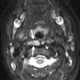

Enlarged lateral retropharyngeal lymph node